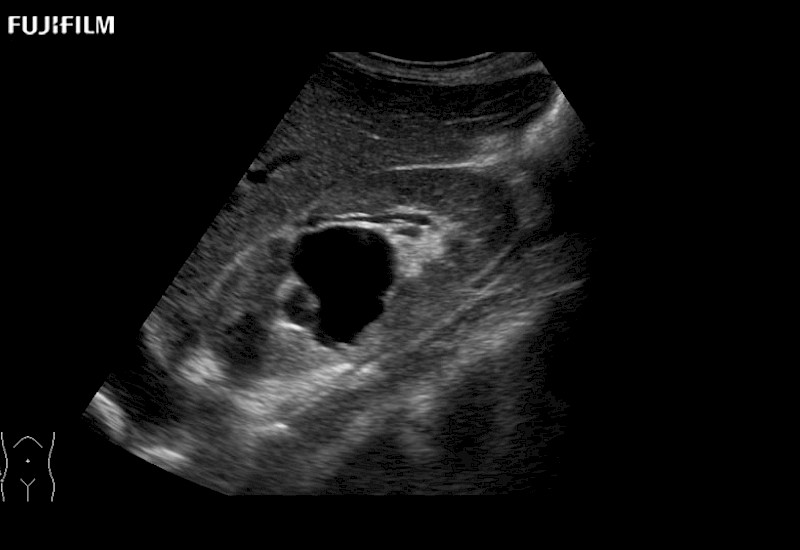

Our dedication to Laparoscopic Surgery allows us to offer superior image quality, outstanding system reliability and intuitive use of cutting edge technology.